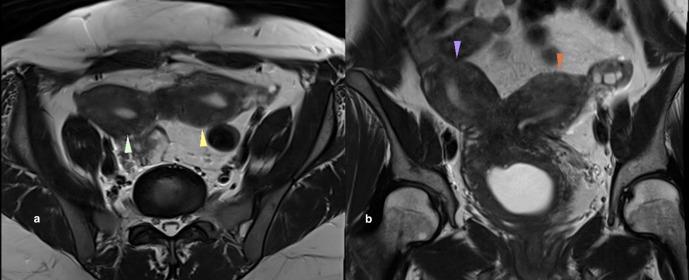

Herlyn-Werner-Wunderlich syndrome is a rare complex congenital anomaly of the urogenital tract involving Mullerian ducts and mesonephric ducts. It is also called OHVIRA syndrome (Obstructed Hemivagina and Ipsilateral Renal agenesis). It is characterized by a triad of uterus didelphys, obstructed hemivagina and ipsilateral renal agenesis. Patients usually present after menarche with pelvic pain, dysmenorrhea, mass, and rarely with primary infertility in later years. We report a case of a multiparous female who presented to the hospital with pain in lower abdomen for the past 2 months and acute retention of urine for 1 day. This is an atypical presentation in a multiparous female that has been described in a single case report so far. Intravenous pyelogram and MRI of the patient revealed uterine didelphys, obstructed right hemivagina causing hematohemicolpos and right renal agenesis. Thorough knowledge of imaging features can enable a radiologist to make a correct diagnosis even in an atypical presentation.

赫林-韦纳-温德利希综合征是一种罕见的泌尿生殖道复杂先天性异常,累及苗勒管和中肾管。它也被称为OHVIRA综合征(梗阻性半阴道和同侧肾缺如)。其特征为双子宫、梗阻性半阴道和同侧肾缺如三联征。患者通常在初潮后出现盆腔疼痛、痛经、肿块,后期很少出现原发性不孕。我们报告一例经产妇,因过去2个月下腹部疼痛和1天急性尿潴留入院。这是经产妇的非典型表现,迄今为止仅在一篇病例报告中有描述。患者的静脉肾盂造影和磁共振成像显示双子宫、梗阻性右半阴道导致阴道积血和右肾缺如。即使在非典型表现中,对影像学特征的全面了解也能使放射科医生做出正确诊断。